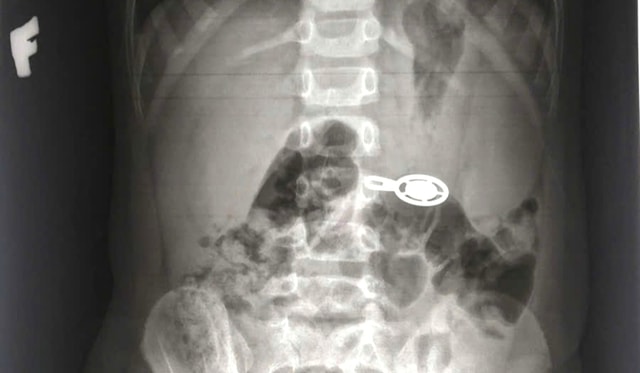

Kết quả X-quang cho thấy dị vật cản quang nằm ở vùng bụng ngang đốt sống L3. Các bác sĩ nhanh chóng chỉ định nội soi gây mê để gắp dị vật.

Ca thủ thuật diễn ra thuận lợi, dị vật được lấy ra là móc khóa dây kéo balo kích thước khoảng 2x3cm. Sau can thiệp, sức khỏe bệnh nhi ổn định.